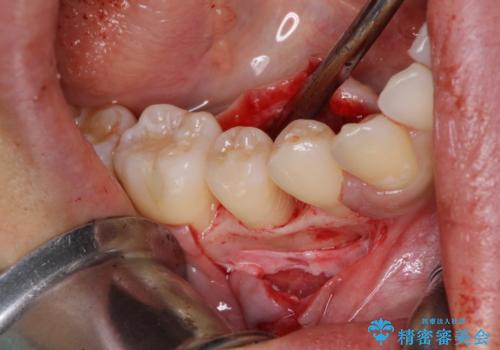

患者様は、他院で右下の歯を抜歯かもと言われました。全体の歯周病はなく、右下の1歯だけ骨が極端に減少していました(初診時歯周ポケット7mm。通常は3mm以下。)。その歯だけ咬合が強いことが原因と考えられたため、咬合を弱くする処置と減少した骨を再生する処置が必要になりました。

骨の再生治療手術をして10か月経過観察をしたのち、骨を平坦化する手術を行い、治療終了となりました。